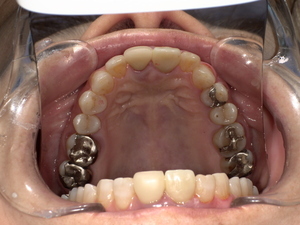

After(治療後)

ジルコニアセラミッククラウンを装着することで、自然な見た目を回復し、しっかり噛める状態に改善しました。

患者様にも「自然な歯のようで違和感がない」とご満足いただきました。